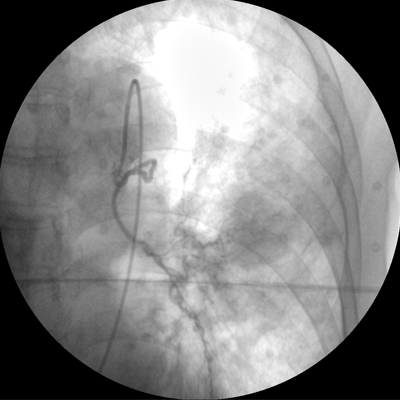

Clinical picture

臨床圖片